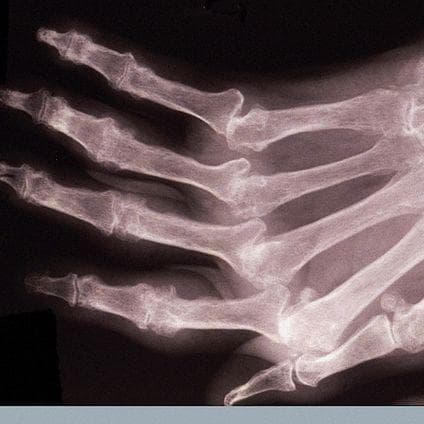

Cracking Fingers Nobel Prize . Unger, of thousand oaks, california, usa, for investigating a possible cause of arthritis of the fingers, by diligently cracking the knuckles of his left hand — but. Evidence for whether the doctor himself was cracked may be that he traveled all the way from his california home to harvard university to pick up his ig nobel prize in. Unger from thousand oaks in california who cracked the knuckles of his left hand every day for over sixty years. For more than 60 years, a californian doctor called donald unger.